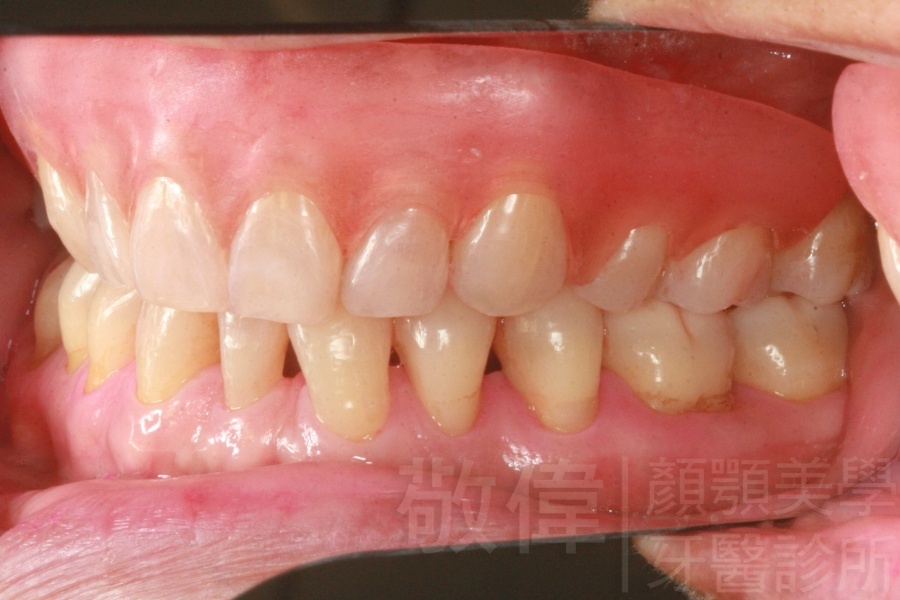

齒顏矯正/戽斗臉型 變身 大帥哥

矯正前-右   矯正前-正   矯正前-左

矯正後-右   矯正後-正   矯正後-左

<個案說明>

戽斗(學名第三級咬合 class III)矯正之後,戽斗的樣子就比較沒有了。最主要的改變是在牙齒的咬合。從側面比較,治療前、治療後的臉型 可更明顯看出來 戽斗的感覺 減少了很多。